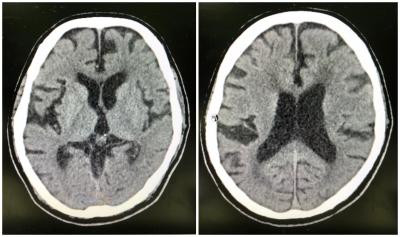

Neuroleptic Malignant Syndrome in an Elderly

Woon LSC

Nazirah A

Mohd Muhaimin MH

HATTA S

Wan Asyraf wz

antipsychotic

delirium

elderly

haloperidol

neuroleptic malignant syndrome

vascular Parkinsonism